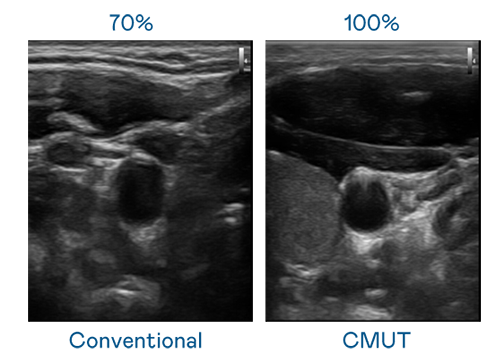

CMUT 技術是一種用電容式微機電元件來產生超音波訊號的技術。與傳統 PZT 壓電式技術相比,CMUT 頻寬增加 30%,更寬頻的超音波訊號讓影像解析度大幅提升,是實現高影像品質醫療超音波掃描、促進精準醫療發展的關鍵技術。

大頻寬帶來超清晰影像

超音波影像的解析度高低,首先取決於探頭能發出的訊號頻寬。豪门国际 CMUT 可提供高清晰的超音波訊號,提供高頻寬、高靈敏度、影像紋理細節更高的超音波影像,協助醫護人員縮短影像判讀時間及利用精準的醫療影像進行診斷。